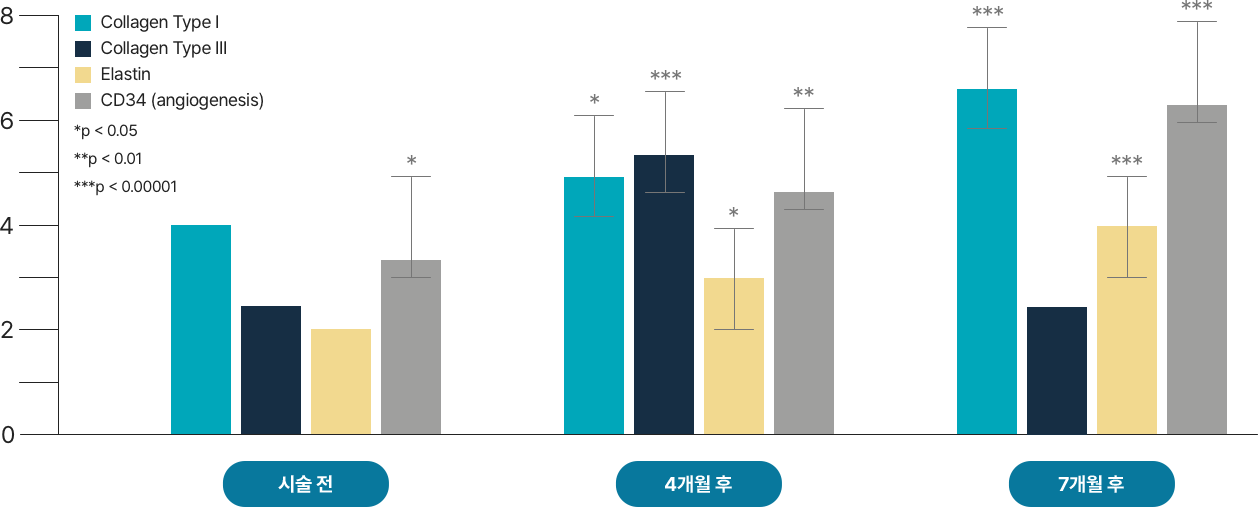

레디어스의 CaHA는 바이오 스티뮬레이터로

ECM 구성 성분 5가지를 만들어냅니다.

5가지 재생 성분은 약해진 피부 중심을 단단히 채워줍니다.

피부에 주입시켜 섬유아세포의 활성과 텐션을 회복하는 것은 바이오 스티뮬레이터인 레디어스의 가장 큰 특징입니다.

피부 탄력성, 두께감, 피부결 개선

조직회복, 콜라겐 1형의 구조적 지지

피부 탄력성, 피부 탄탐함

수분 보충, 피부 탄탄함

혈액 공급, 영양분 공급

시술 직후, 피부와 주변 조직이 건강하게 재생되기 시작하고 콜라겐을 비롯한 탄력 성분들이 자연스럽게 활성화되며 피부 세포의 기능이 점차 정상화됩니다.

이러한 과정을 통해 피부는 다시 탄력을 찾고, 시간의 흐름에 맞서 되돌리는 듯한 턴에이징 효과를 경험하게 됩니다.